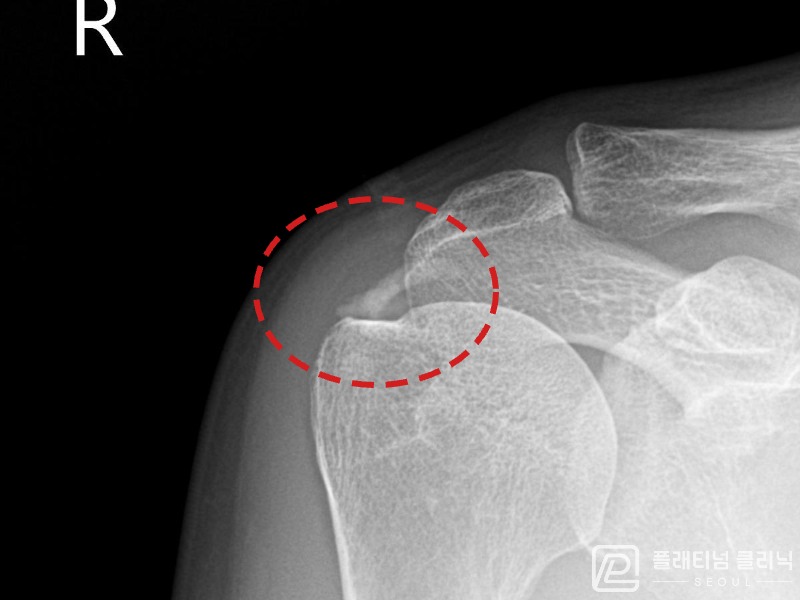

[촬영시기:21.09.02~21.10.07]

[석회분쇄흡입술] 좌측 어깨 통증으로 팔을 옆으로 올리기 어려워진 60대 남성 환자로, X-ray에서 좌측 극상근건 내 석회 침착이 확인되어 석회분쇄흡입술을 시행하였습니다.